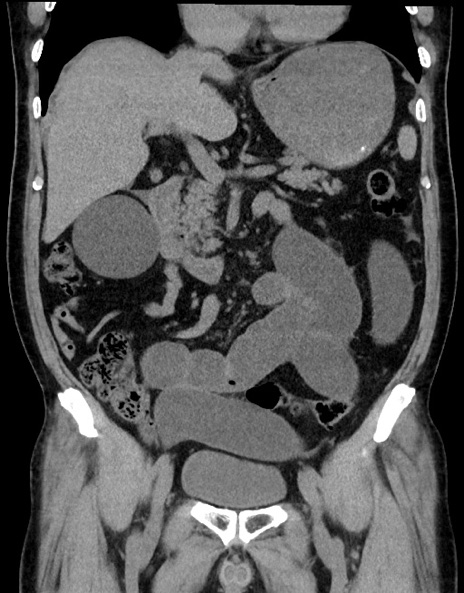

症例15(冠状断像)

【症例】70歳代男性

【主訴】腹痛

【現病歴】今朝から腹痛あり。全体的に痛い。特に左上の方。排ガスが今日はない。冷や汗が出る。

【既往歴】直腸癌術後

【身体所見】左側腹部〜上腹部に圧痛あり。腹膜刺激症状明らかなではない。軽度反跳痛。左下腹部に術後瘢痕あり。

【データ】WBC 7700、CRP 0.02